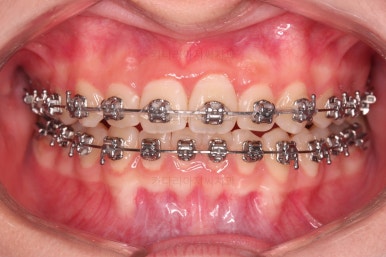

장치 부착 직후의 눈에 보이는 모습과 옆라인의 변화 확인해 주시고요.

가지런한 느낌은 좋아졌고, 과개교합도 깔끔하게 개선이 되었습니다.

교합이 개선됨에 따라 자연스럽게 중앙선도 좋아지고 있는 부분이 눈에 띄고요.

부정교합이 정말 많이 좋아졌습니다.

종료 때의 사진입니다.

가지런하고, 교합도 좋으며 과개교합이나 앵글씨 2급 부정교합 부분도 완벽히 좋아졌습니다.

자연스럽게 중앙선도 매우 좋아졌고요.